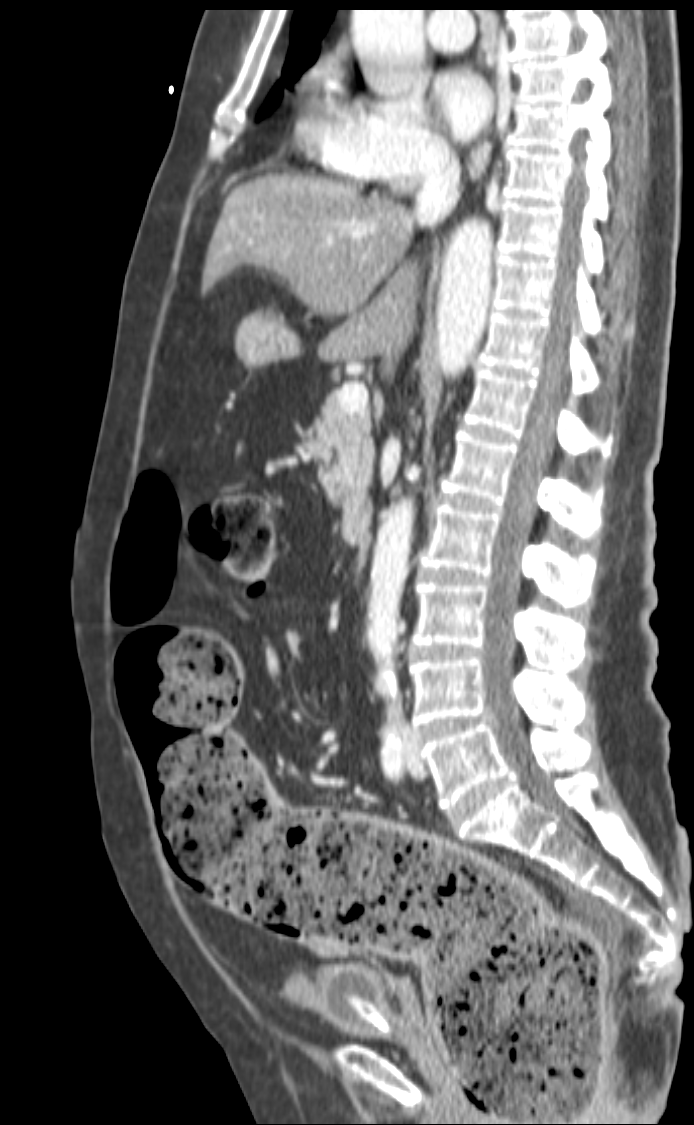

El íleo biliar se define como la obstrucción mecánica causada por la impactación en el lumen intestinal de una litiasis biliar procedente de la vesícula. Es una complicación que ocurre en el 0.3 – 0.5% de todas las colelitiasis.

Aunque su frecuencia global es baja, en pacientes ancianos no lo es tanto, llegando a constituir alrededor del 25% todas las obstruciones intestinales no estranguladas. Al igual que en la coletitiasis, es más frecuente en mujeres.

Su mortalidad varía entre el 8 -30%, llega a ser bastante alta sobre todo en ancianos con patología concomitante.

Placa simple: Triada de Rigler: Obstrucción de asas de delgado + gas en el arbol biliar + litiasis (frec en la FID); estos tres hallazgos constituyen la Triada de Rigler.

Tomografía computarizada: S y E del 93% y 100% respectivamente. Hallazgos: Dilatación por obstrucción de asas de delgado. Aerobilia. Litiasis (2 – 3 cm aprox). Hay que tener cuidado ya que muchas litiasis no están calcificadas y su densidad puede ser similar al contenido del intestino. Pueden ser multiples, por tanto hay que poner atención para que no pasen desapercibidas y evitar las recidivas. Fistulas (normalmente entre vesícula y duodeno). Neumoperitoneo (gas portal o gas mural indican peor pronóstico).

Sindrome de Bouveret: Es un tipo de íleo biliar muy proximal y poco frecuente, donde una litiasis migra a través de una fístula desde la vesícula biliar al duodeno proximal o al píloro gástrico, produciendo ahí una obstrucción.